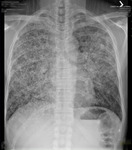

Pneumocystis jirovecii pneumonia

Posteroanterior chest x-ray showing severe, bilateral pulmonary interstitial infiltrates with pneumatoceles

From the collection of Matthew Gingo, UPMC